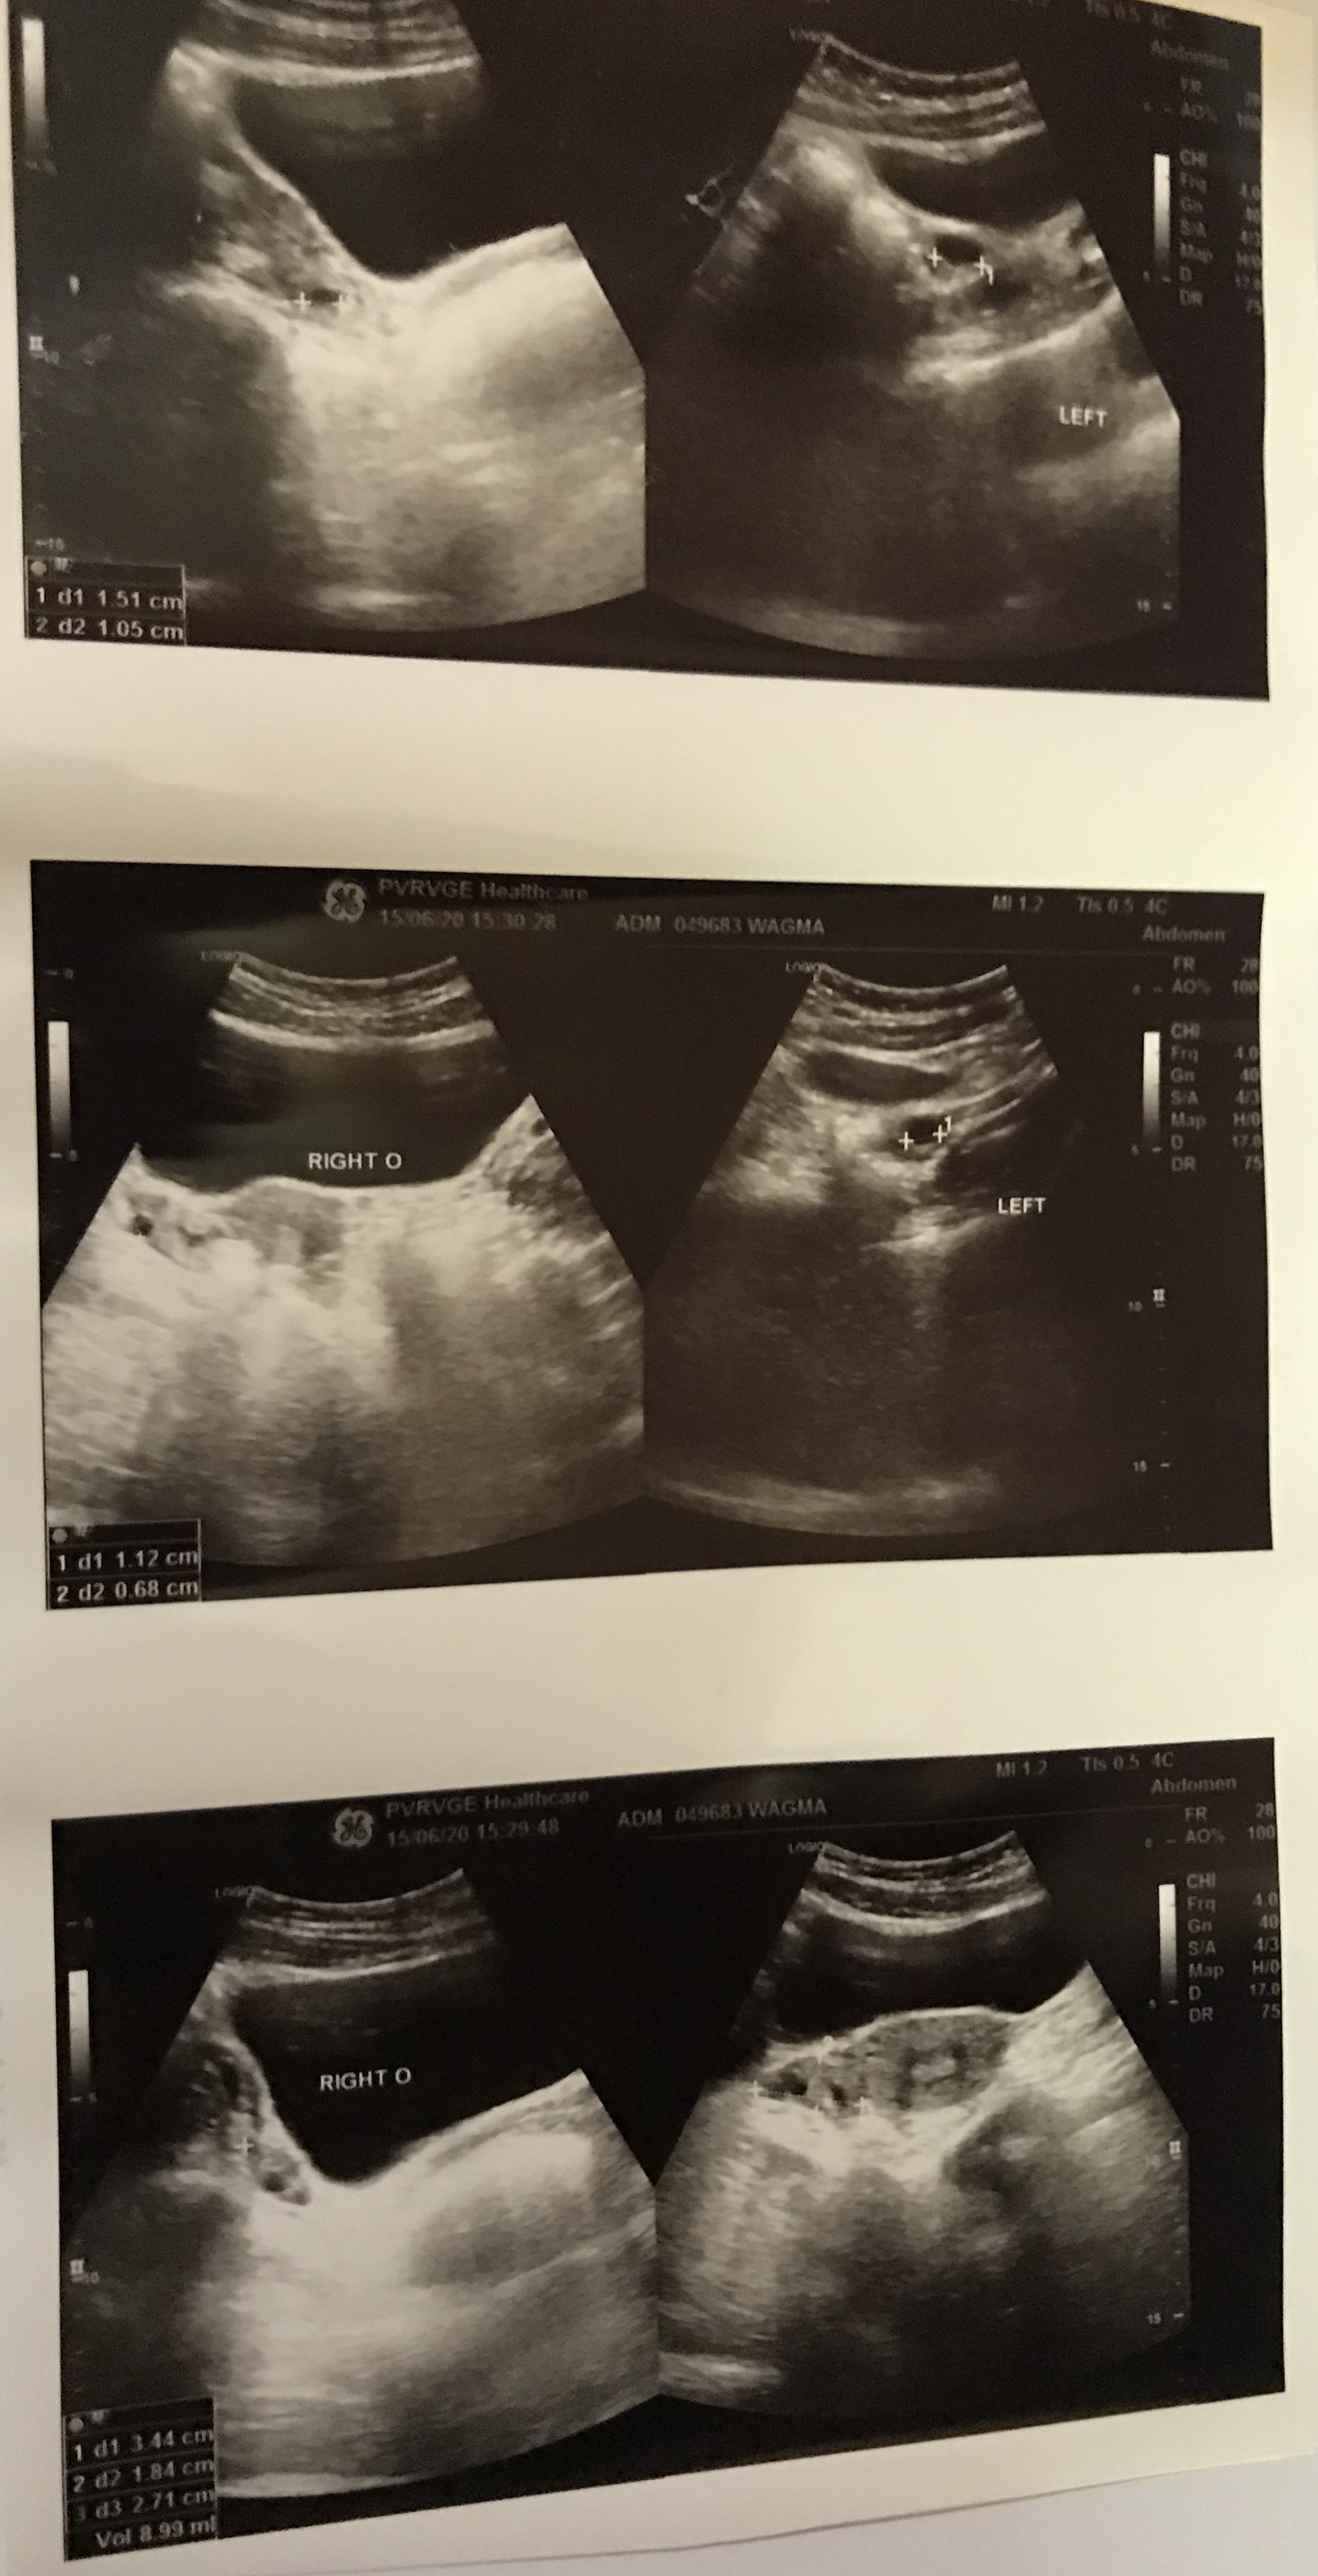

Dr i m attaching my todays pelvic ultrasound report, kindly can u tell me if its fine

#2

#3

#4

Mam i had a pelvic ultrasound just before ramadan .it was a normal ultrasound .

Can pcos emerge in 1-2months?